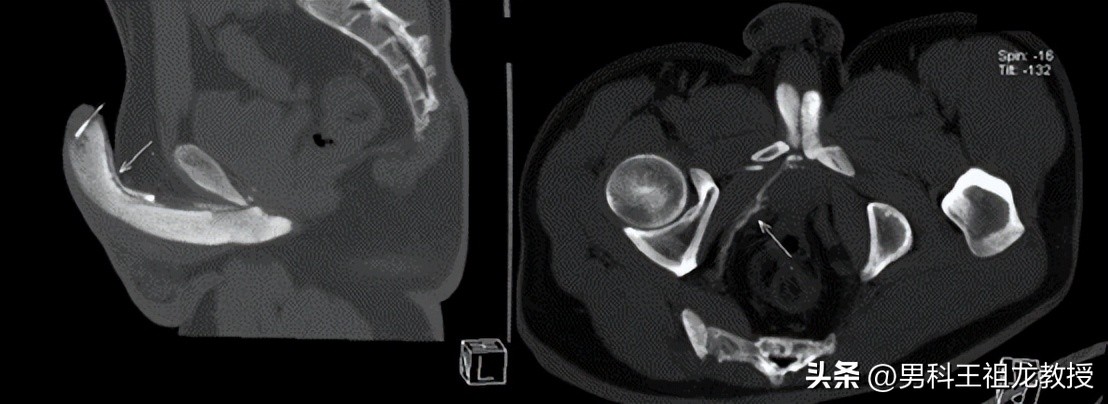

三维重建图

在王祖龙主任的指导下由我科医生为患者行阴茎海绵体血管活*药性**物注射,待其完全勃起后推注造影剂,并在放射科王道清主任及程留慧主任的大力支持下,为患者完成了CT扫描及三维血管重建。

影像表现可见 :阴茎右侧海绵体较左侧充盈差,右侧海绵体脚静脉、阴部内静脉及右侧髂内静脉显影。阴茎远端背深静脉显影显著。